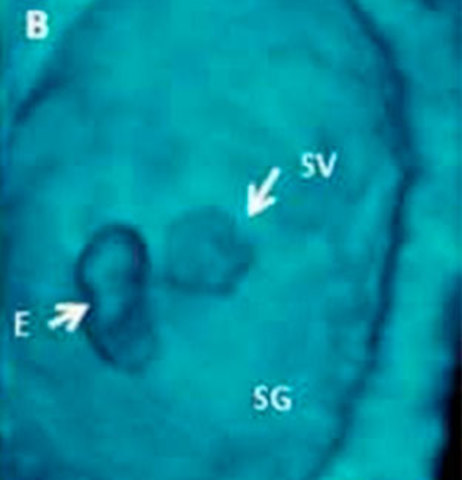

• SEMANA 24

SEMANA 24

El contorno del bebé es más redondeado en la semana 24 de embarazo: sugiere las formas más regordetas del recién nacido. Ya pesa entre 500 y 600 gramos y puede llegar a los 21 centímetros de longitud.

Tu hijo flota en el agua, ya que todavía el saco amniótico es muy espacioso. Esto permite al bebé moverse de un lado a otro, darse la vuelta, girarse, dar patadas y cambiarse de posición varias veces en un día